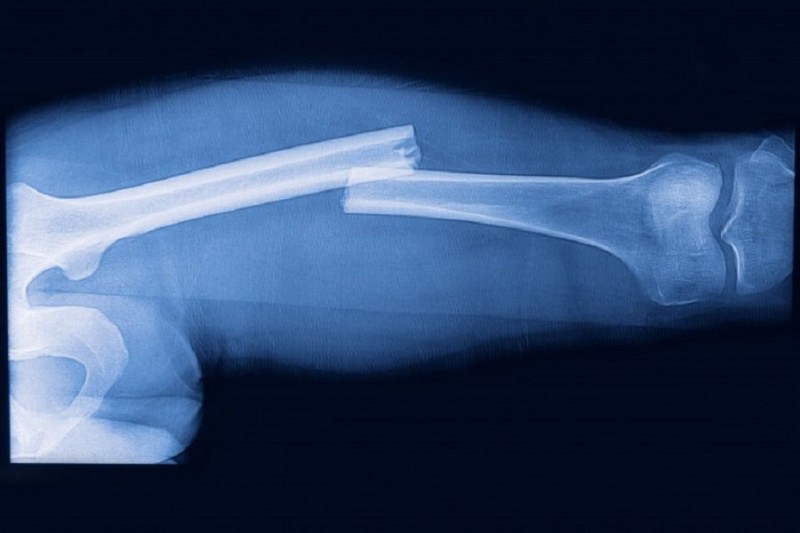

Зачастую у людей случается перелом верхних конечностей, при неожиданном падении или сильном ударе. Первым долгом нужно иммобилизировать руку, чтобы предотвратить превращение закрытого перелома в открытый. Для этого, к руке требуется приложить любой подручный материал, который может быть доской, фанерой, толстой веткой, и зафиксировать. Руку, с шиной из подручного материала, требуется держать в согнутом положении, подвесив её на платке, шарфе, бинте, протянув через шею.

В случае открытой травмы руки, нужно сразу остановить кровотечение, при помощи наложения жгута на то место, которое расположено выше открытой травмы. Для исключения попадания инфекции в рану, полученную в результате травмы, её нужно обработать любым антисептиком, а далее руку нужно зафиксировать.